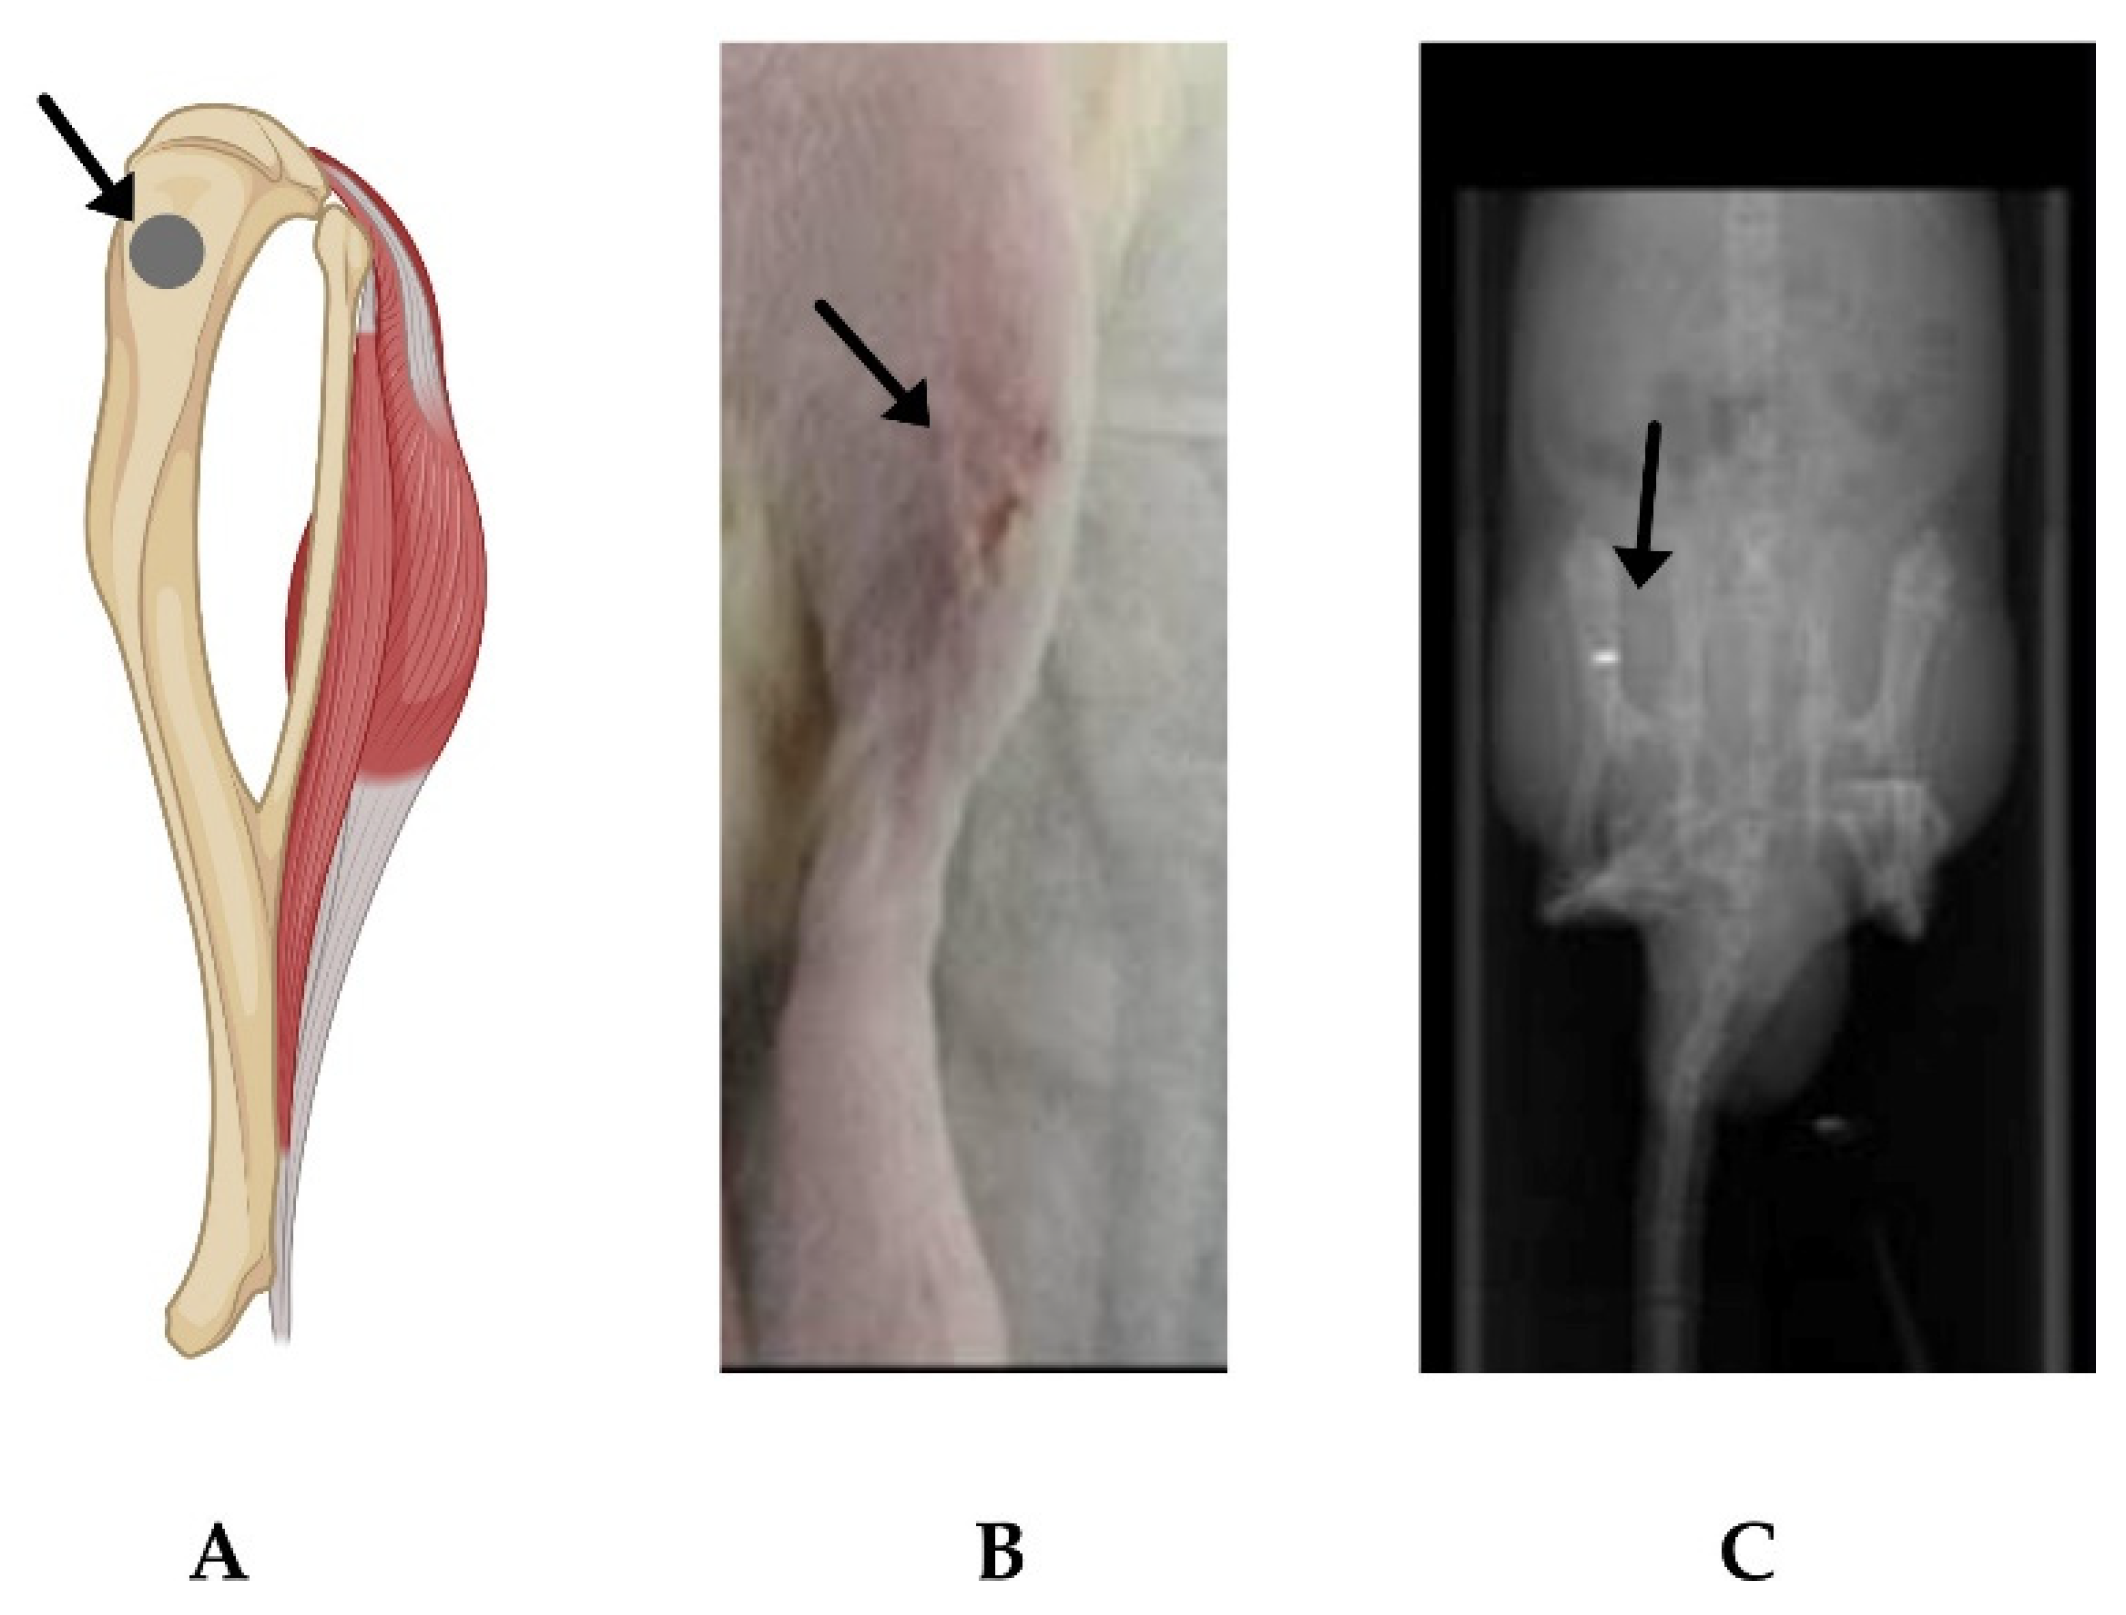

2.2. In Vivo Evaluation of α-MSH-SM-Liposomes

4.6. Imaging of α-MSH-SM-Liposomes